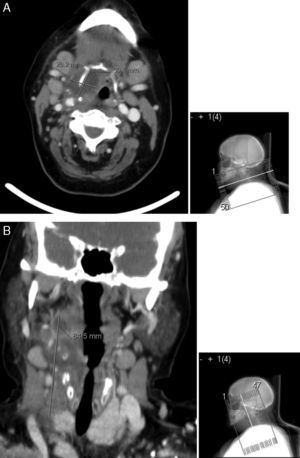

Cerca de 10 dias após a alta recorreu de novo ao serviço de urgência do nosso centro hospitalar por dor e tumefacção ao nível da região tiroideia com rubor e flutuação, sem febre nem compromisso respiratório. Analiticamente, apresentava parâmetros sistémicos de inflamação e a ecografia mostrou coleção cervical anterior volumosa, cujos planos mais profundos não eram acessíveis por ecografia. Efetuou TC cervical que revelou celulite cutânea e volumoso abcesso nos planos anteriores do pescoço, com cerca de 12cm de extensão, sendo o seu diâmetro transversal máximo de cerca de 45mm e estendendo‐se desde o plano imediatamente abaixo do maxilar inferior até quase ao plano das clavículas (fig. 4). Foi internada no serviço de otorrinolaringologia e submetida a nova drenagem cirúrgica, que decorreu sem intercorrências. O exame histológico do material suspeito identificou alterações compatíveis com processo inflamatório agudo necrosante, e as culturas bacteriológicas, micológicas e micobacteriológicas do pús foram negativas. No dia seguinte, por manter drenagem purulenta, fez‐se incisão inferior do pescoço, para permitir drenagem mais eficaz sem acumulação de pús no fundo de saco inferior, e iniciou antibioterapia endovenosa com imipenem/cilastatina, que manteve durante 8 dias. Os procedimentos decorreram sem intercorrências pós‐operatórias e a TC cervical, uma semana após admissão, revelou apenas densificação dos planos cervicais anteriores, pré‐osso hioide e anteriormente à cartilagem tiroide, em relação com alterações inflamatórias/pós‐cirúrgicas, gânglios cervicais reativos, sem evidência de coleções cervicais e sem alterações tomodensitométricas das glândulas tiroideia, submandibulares e parótidas. A doente evoluiu clínica e analiticamente de forma favorável, tendo tido alta para consulta externa, com bom controlo glicémico sob insulinoterapia.